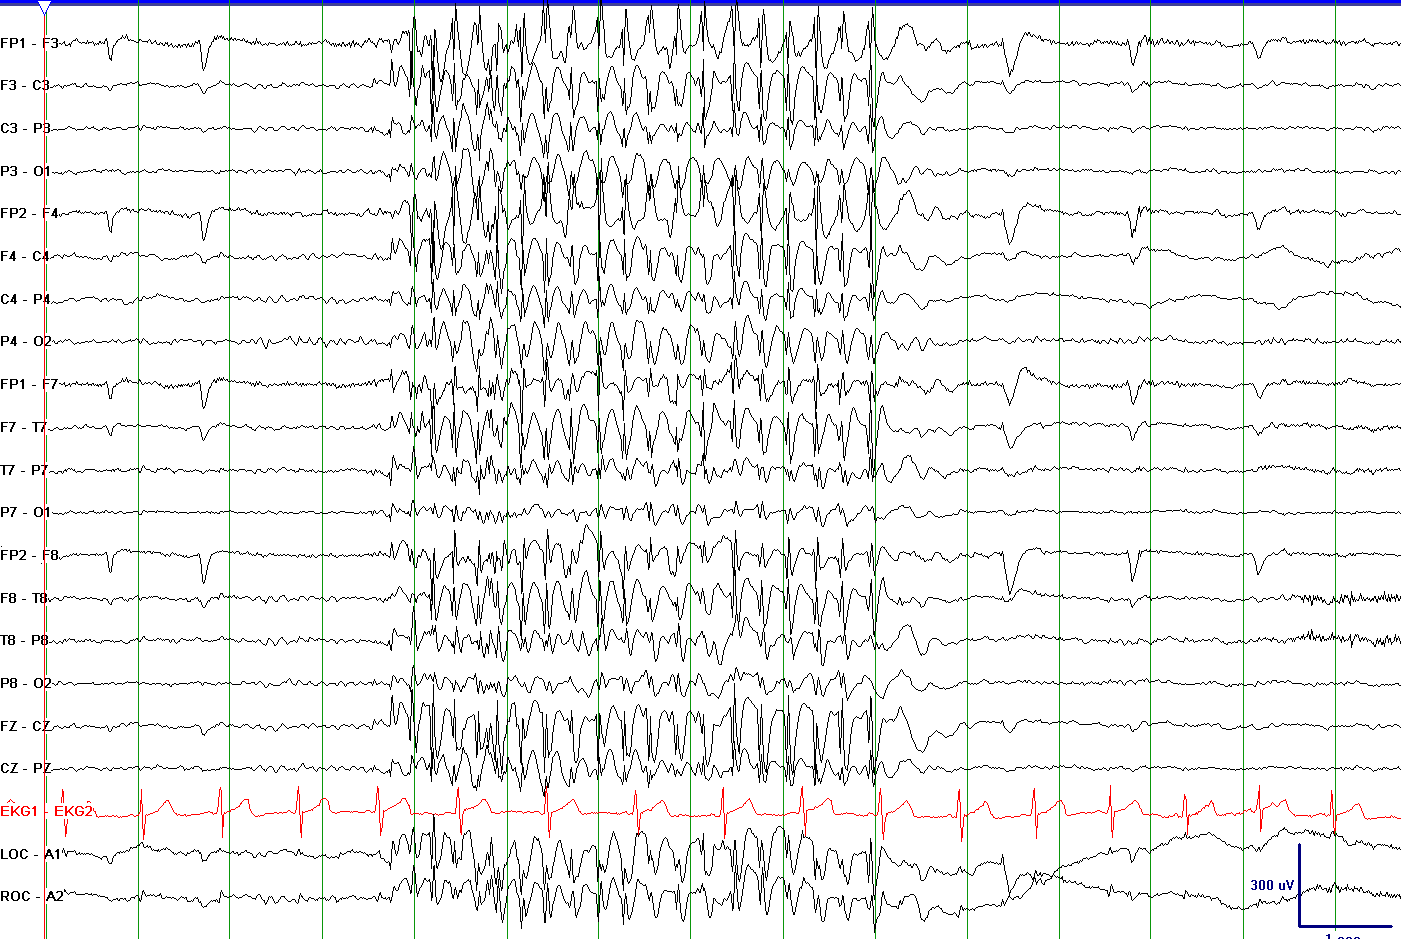

• An EEG (electroencephalogram) is done to look for possible seizure activity. Hyperventilation and photic stimulation (exposure to rapid flashing lights) are often performed during the EEG. The EEG shows generalized polyspike or spike and wave discharges at 3-4 Hz (cycles per second).

• The EEG shows spike and wave discharges at 3 to 6 Hz (cycles per second) that are generalized (the same on both sides of the brain).

EEG 3 To 6 1

EEG 3 To 6

Examples of 3 to 4 Hz generalized spike wave